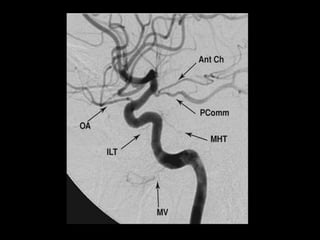

-Branches : 3 Groups

1-The Meningohypophyseal Trunk (MHT)

2-The Inferolateral Trunk (ILT)

3-The Capsular Arteries of McConnell

4-Intradural Portion